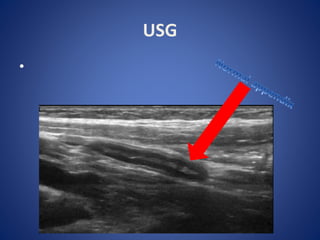

USG

•

Inflamed appendix on U/S

US Scans • Sensitivity= 85% Operator based • Specificity > 90% • AP dia appendix > 7mm • CROSS SECTIONAL VIEW: - Thick walled - Non compressible luminal structure : Target Lesion • Periappendiceal fluid/ Mass